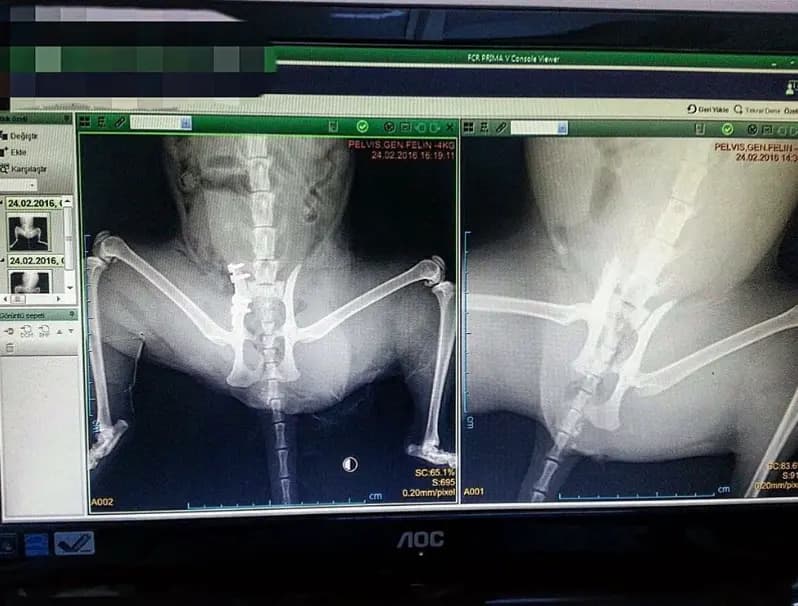

Kliniğimizde başarıyla gerçekleştirdiğimiz kalça operasyonu vakası. Bu vaka, kedilerde kalça problemlerinin cerrahi tedavisinde kullanılan Femoral Head Ostectomy (FHO) prosedürünü göstermektedir. Femoral Head Ostectomy (FHO), kedilerde kalça displazisi, kalça çıkığı, femur başı nekrozu veya travmatik kalça yaralanmaları gibi durumlarda uygulanan cerrahi bir tedavi yöntemidir. Bu operasyonda, femur başı (femoral head) çıkarılır ve yeni bir sahte eklem oluşturulur. Operasyon Süreci: • Genel anestezi altında gerçekleştirilir • Kalça eklemi cerrahi olarak açılır • Femur başı ve boynu çıkarılır • Yumuşak doku ile yeni bir sahte eklem oluşturulur • Metal implantlar (vidalar) ile stabilizasyon sağlanır Röntgen görüntülerinde: • Ventrodorsal (VD) ve lateral projeksiyonlar görülmektedir • Metal implantlar ve vidalar net bir şekilde görülmektedir • Femur başlarının çıkarıldığı görülmektedir • Kemik yapılarının iyi hizalandığı görülmektedir Postoperatif Bakım: • Ağrı yönetimi • Fizik tedavi ve rehabilitasyon • Hareket kısıtlaması • Düzenli kontroller Bu vaka, kliniğimizin kedilerde kalça cerrahisi konusundaki deneyimini ve başarısını göstermektedir. Operasyon sonrası hasta başarıyla iyileşmiş ve normal yaşam kalitesine dönmüştür.